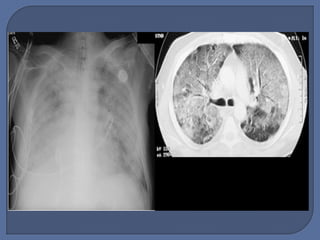

 Incidence Higherthan Past Estimates 150,000 – 200,000 per year in US alone. • Sepsis most common associated cause • Mortality persists at 30-45% • Current Rx is supportive only • There remains a major need for novel therapeutic strategies to treat ARDS.